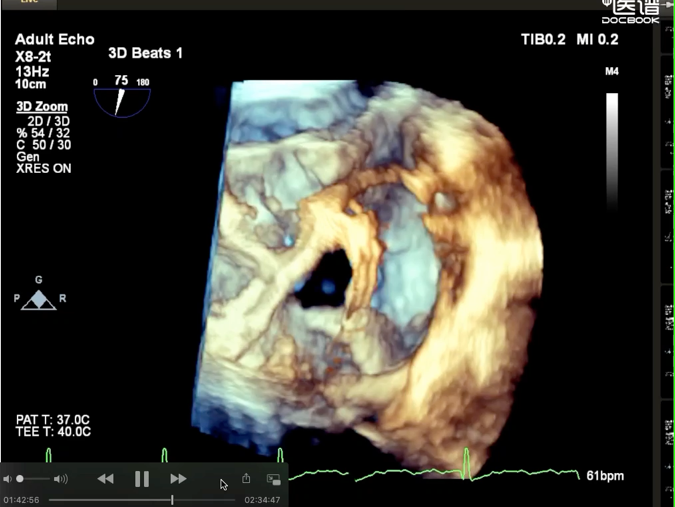

术后超声

轻中度三尖瓣反流(1~2+)。